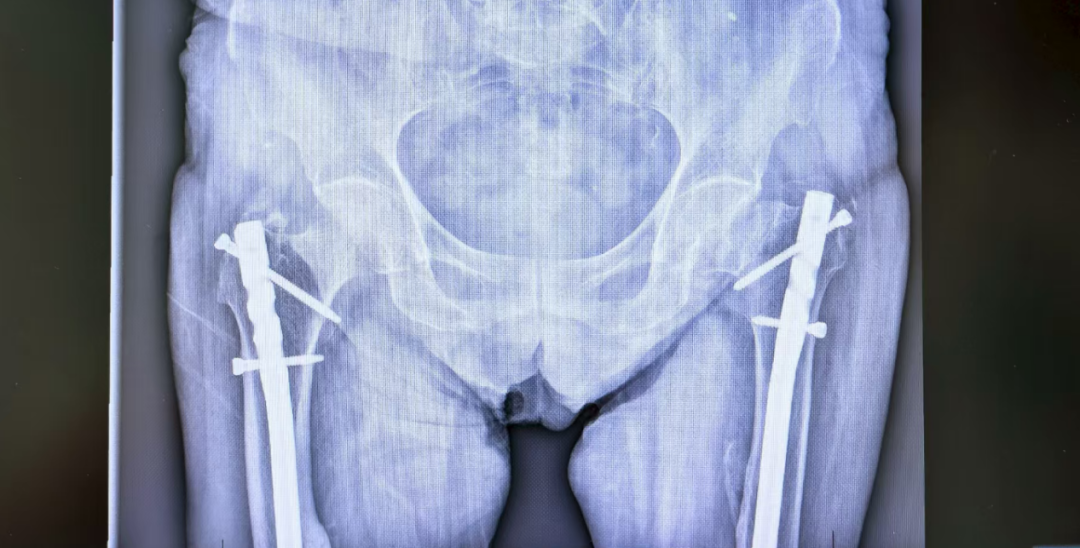

几年前,一位 85 岁的老奶奶同样被确诊为「异位甲旁亢」,但由于高龄以及家属对手术风险的顾虑,最终选择了保守治疗。可在之后的数年里,她反复发生全身多处骨折,骨盆影像上密密麻麻全是陈旧骨折痕迹,肾脏也长满结石,最后只能依靠轮椅生活,生活质量极差。

「看到片子上的影像,每个医生都会感到惋惜。」张瑜庆的声音低沉下来,「一旦发生严重的骨质疏松和骨折,很多损害是不可逆的。我们不想再看到第二个这样的病例。」